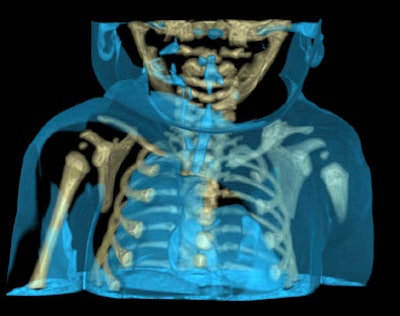

Virtual autopsy often works where traditional autopsy fails, Persson said, offering an example from his institute, which investigated the case of a 3-week-old infant who had died mysteriously in the operating room during a standard laryngoscopy.

"The autopsy couldn't find the cause of death," he said. But CT showed "a very tiny hole," in the heart, the result of an iatrogenic injury during the procedure.

![]() |

| A 3-week-old infant (above) died mysteriously following laryngoscopy, and traditional autopsy was inconclusive. However, CT showed the cause of death to be a puncture wound to the heart evidenced by an air pocket in the organ (below), which resulted from an iatrogenic injury during the laryngoscopy procedure. Images courtesy of Dr. Anders Persson and Patric Ljung. |